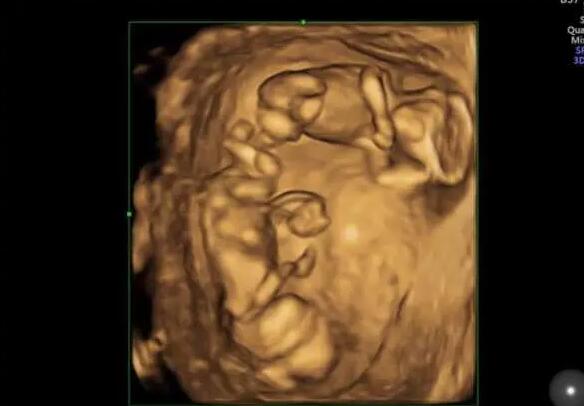

第三代试管婴儿优势众多,能够剔除遗传疾病,实现优生优育。它的出现也让许多大龄女性看到了生育的希望,从事泰国三代试管婴儿服务已经15余年,目前跟当地好几家资深三代试管婴儿医院均有合作,如果自然生育无法帮到你,或许选择三代试管婴儿能够让您成功获得好孕,拥有属于自己的健康宝宝。